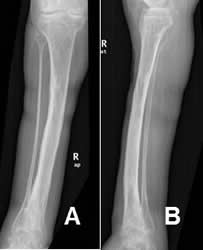

Fig 122. Consolidación retardada.

A: Rx AP. Fractura espiroidea en la tibia, que se manejó con reducción cerrada y estabilización con yeso.

B: Rx AP. Rx de control a los 4 meses, sin formación de callo óseo y los extremos no están en contacto.